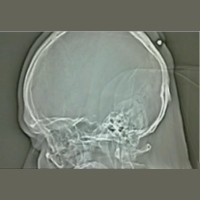

Dikira Kista Ternyata Peluru yang Bersarang di Kepala - detikHealth Jumat, 03 Sep 2010 16:33 WIB Bochum - (mer/ir) Infografis Lainnya Infografis Feeding Difficulty Vs Picky Eating, Apa Beda & Dampaknya bagi BB Anak? Infografis Waspadai Dampak Picky Eating pada Anak, Berikut Cara Jitu Cegahnya Infografis Infografis: Strategi dan Formasi Ideal untuk Menang Lomba Balap Bakiak